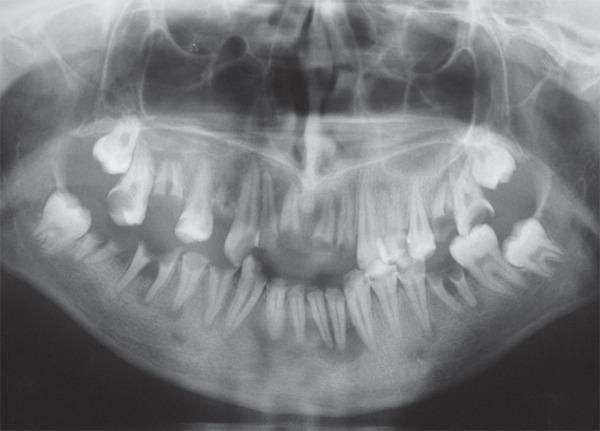

This paper reports the nonsurgical endodontic therapy using calcium hydroxide intracanal dressing and prosthetic treatment of 9 teeth with periapical lesions in a 16-year-old female patient. The periodontal treatment plan included oral hygiene instructions, mechanical debridement and gingivectomy in the maxillary incisors to improve gingival contouring. Root canal treatment was indicated for teeth 11-13, 21, 22, 42-45. After successive changes of a calcium hydroxide intracanal dressing during 6 weeks, the size of the periapical radiolucencies decreased and lesion remission occurred after root canal obturation. The endodontically treated teeth received a bondable polyethylene reinforcement fiber (Ribbond) in the prepared canal space and crown buildup was done with composite resin. Prosthetic rehabilitation was planned with single-unit metal-ceramic crowns and fixed partial dentures. Clinical and radiographic evaluation after 6 months showed successful results. The outcomes of this case showed that chronic periapical lesions can respond favorably to nonsurgical endodontic treatment in adolescent patients and that, with proper indication, polyethylene fibers can provide an effective conservative and esthetic option for reinforcing endodontically treated teeth undergoing prosthetic rehabilitation.

本文报告了一例 16 岁女性患者,9 颗有根尖病变的牙齿接受了非手术根管内氢氧化钙封药治疗和修复治疗。牙周治疗计划包括口腔卫生指导、上颌切牙的机械清创和牙龈切除术,以改善牙龈轮廓。11-13、21、22、42-45 号牙需要根管治疗。经过 6 周的多次更换氢氧化钙根管内封药,根尖的放射性透影区缩小,根管充填后病变缓解。经过根管治疗的牙齿在预备好的根管空间内使用可粘结的聚乙烯增强纤维(Ribbond),并用复合树脂进行牙冠修复。计划采用单冠金属陶瓷冠和固定局部义齿进行修复。6 个月后的临床和影像学评估显示治疗成功。该病例的结果表明,青少年患者的慢性根尖病变可以通过非手术根管治疗获得良好的效果,并且在适当的适应证下,聚乙烯纤维可以为接受修复治疗的根管治疗后牙齿提供一种有效的保守和美观选择。